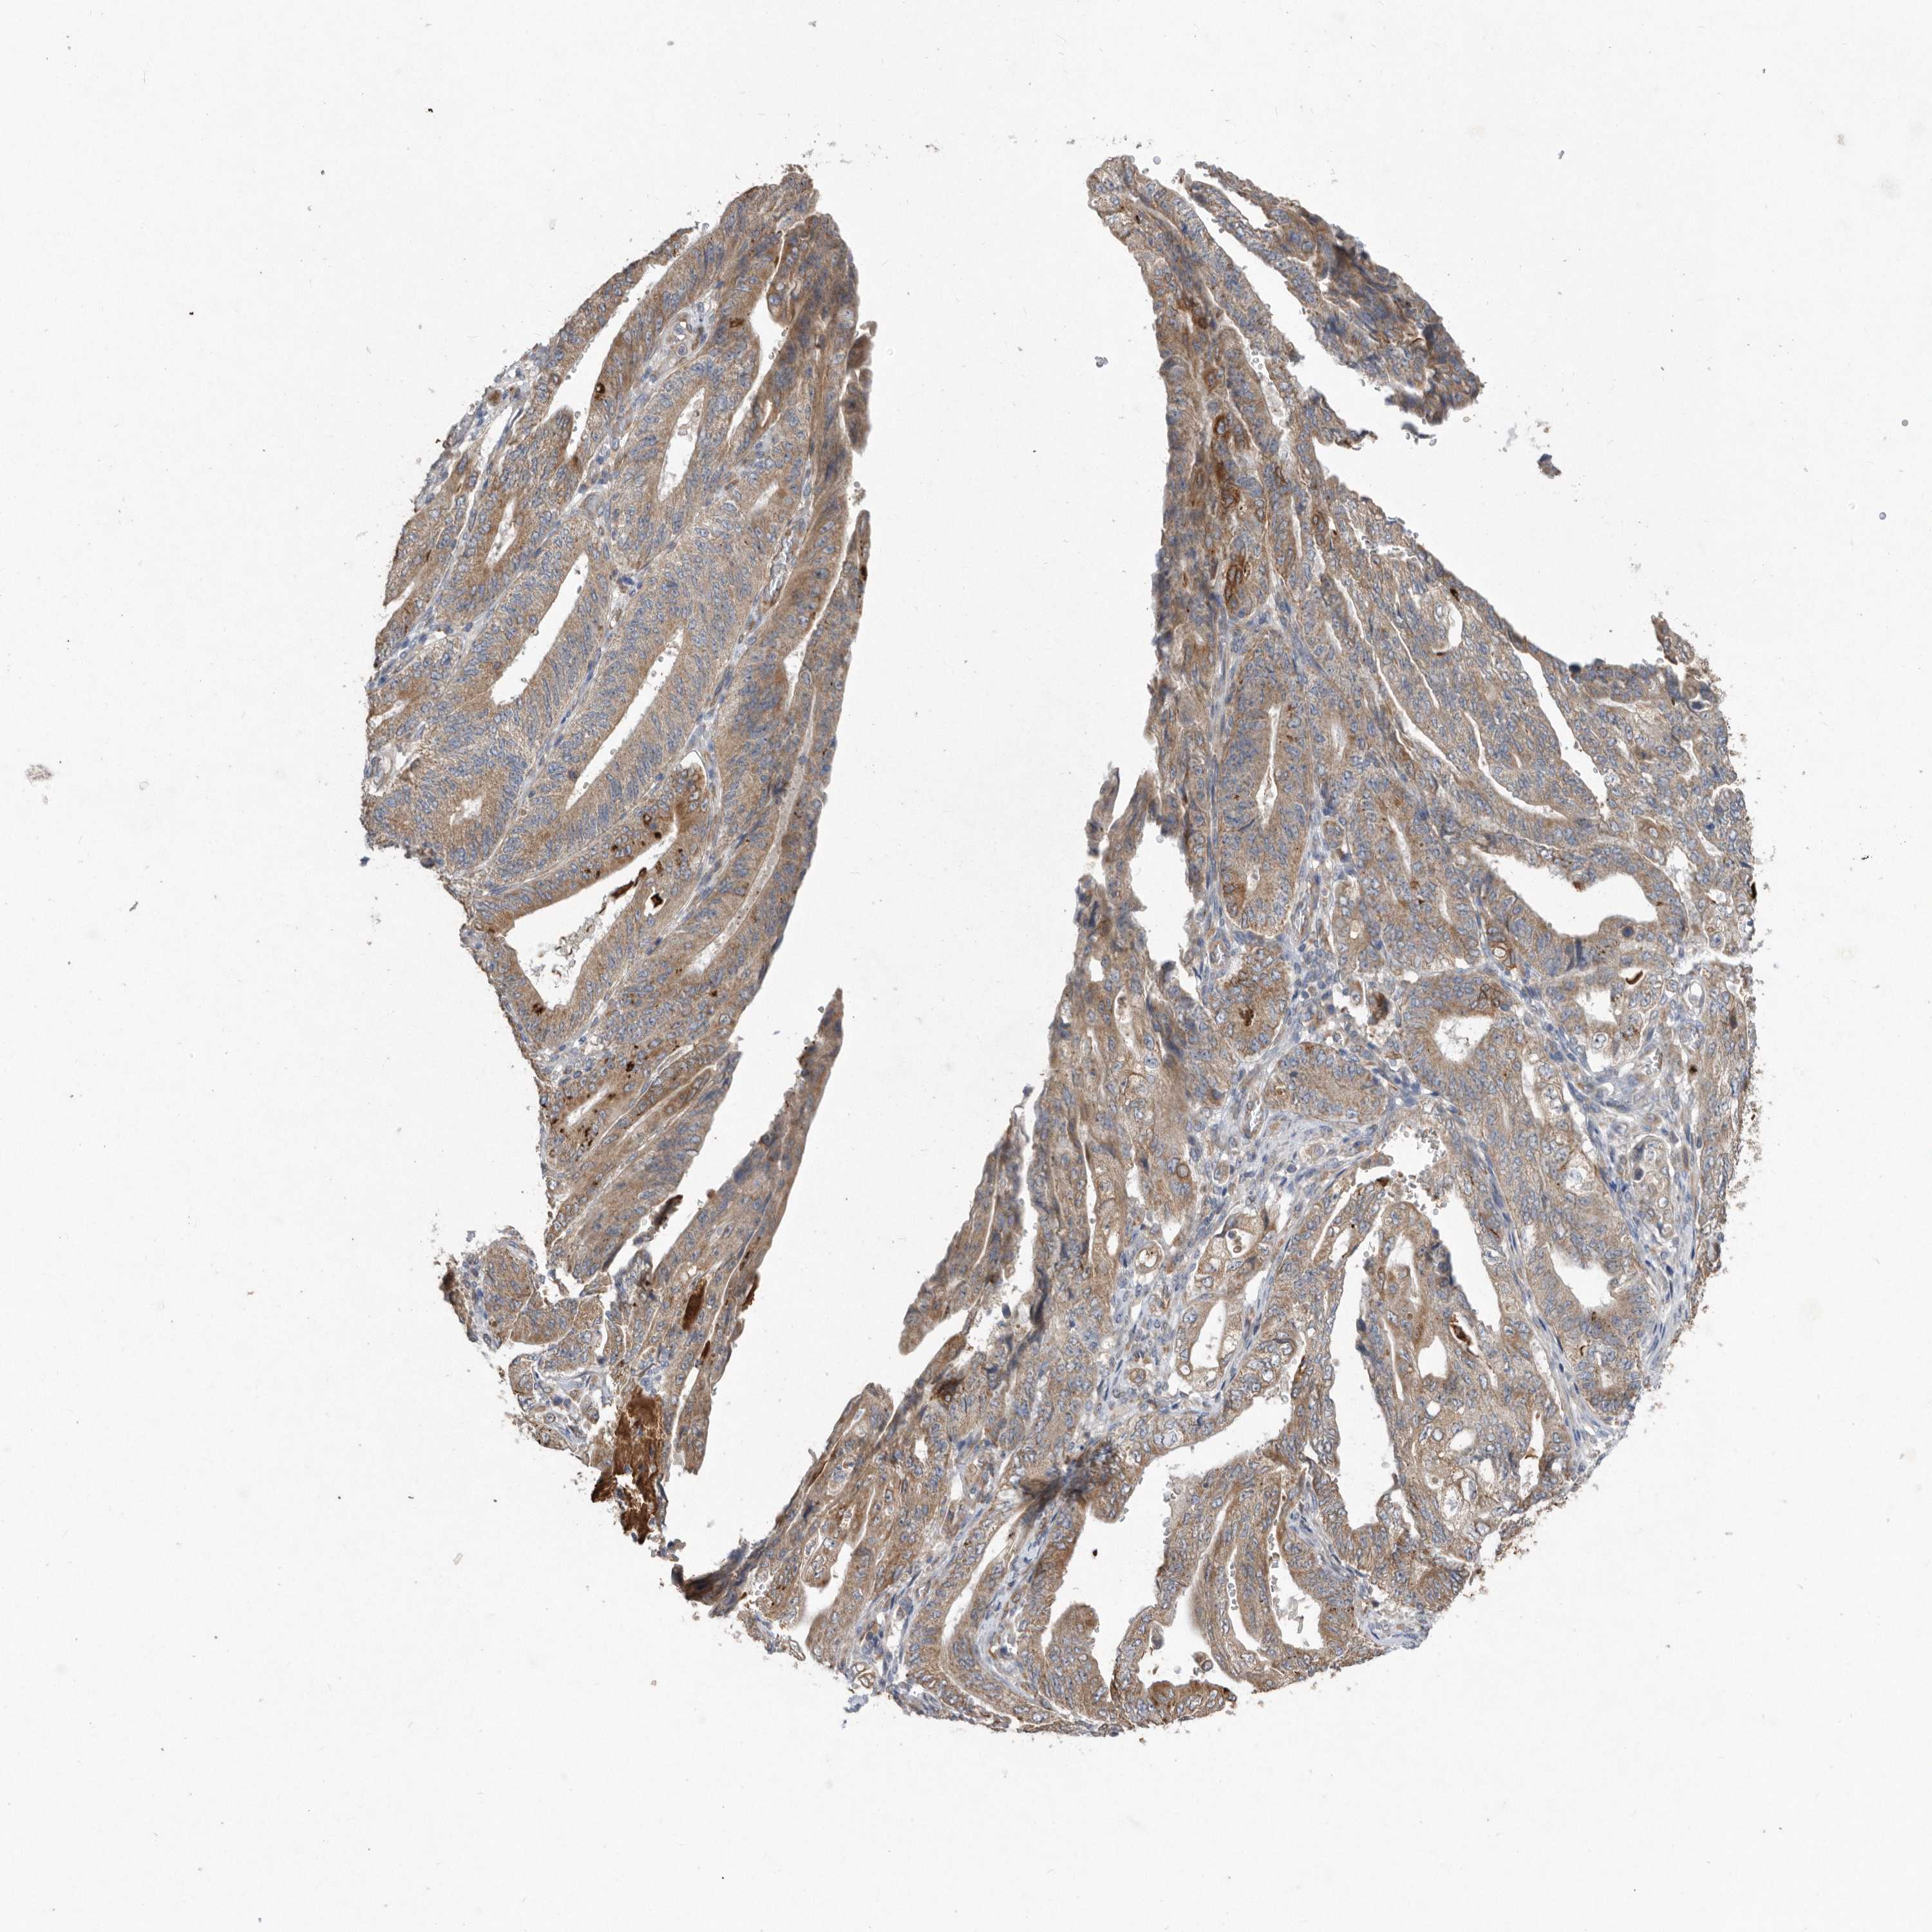

STOMACH CANCER - Protein expressioni

A mouse-over function shows sample information and annotation data. Click on an image to view it in a full screen mode. Samples can be filtered based on level of antibody staining by selecting one or several of the following categories: high, medium, low and not detected. The assay and annotation is described here.

Note that samples used for immunohistochemistry by the Human Protein Atlas do not correspond to samples in the TCGA dataset.

Antibody stainingi

Antibody staining in the annotated cell types in the current human tissue is reported as not detected, low, medium, or high, based on conventional immunohistochemistry profiling in selected tissues. This score is based on the combination of the staining intensity and fraction of stained cells.

Each image is clickable and will lead to virtual microscopy that enables deeper exploration of all samples and also displays staining intensity scores, fraction scores and subcellular localization as well as patient and tissue information for each sample.

Antibody HPA029193

Antibody CAB025430

Staining

High

Medium

Low

Not detected

Intensity

Strong

Moderate

Weak

Negative

Quantity

>75%

75%-25%

<25%

None

Location

Nuclear

Cytoplasmic/membranous

Cytoplasmic/membranous,nuclear

Adenocarcinoma, NOS

Adenocarcinoma, High grade